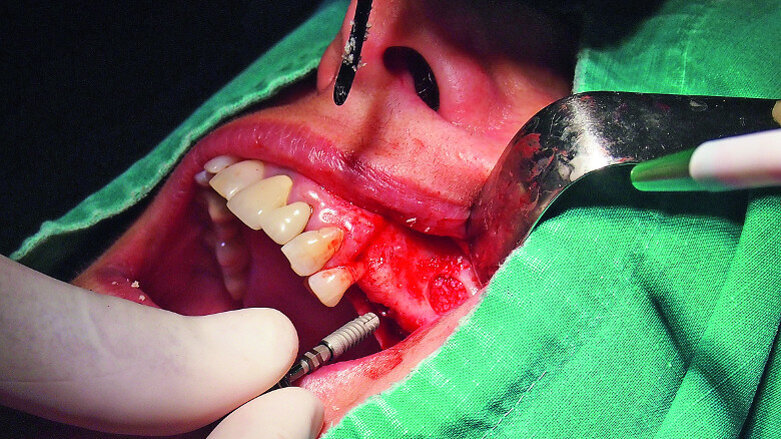

Fig. 18: Placement of two GC Aadva Standard implants with regard to the future restorative margins.

A demonstration of this technique is shown in Figures 13 to 20. This case presents an elderly woman who had lost her teeth in the lateral mandible decades ago. Being a healthy non-smoker with good oral hygiene, no history of periodontal disease and low masticatory forces, she was an adequate candidate for bone grafting together with implant placement. The future restorative margins allowed the usage of ridge splitting (Figs. 13 & 14). Therefore, we opted for a ridge split with vertical releases carried out utilising a partial-thickness flap. The periosteum was left attached in order not to impede the perfusion of the buccal plate (Fig. 15). After ridge splitting, the buccal and lingual plates were separated with the use of bone spreaders (Split-Control Plus, Meisinger) to allow the placement of two GC Aadva Standard implants, one of 3.3 mm in diameter and 8.0 mm in length and the other measuring 4.0 mm in diameter and 8.0 mm in length (Figs. 16–18).